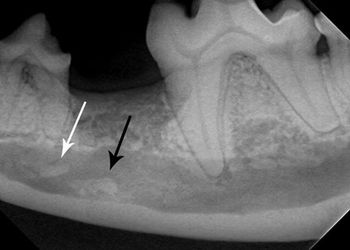

Two case examples display how radiography can reveal hidden pathology.

Correct management of periodontal patients in veterinary practice demands a thorough understanding of veterinary dental radiographic anatomy, periodontal probing and many times open evaluation and direct visualization of diseased areas. Stage III periodontal disease in particular requires advanced skills and familiarization with periodontal pathophysiology to make decisions to attempt to grow new supportive tissue adjacent to compromised teeth or extract them.